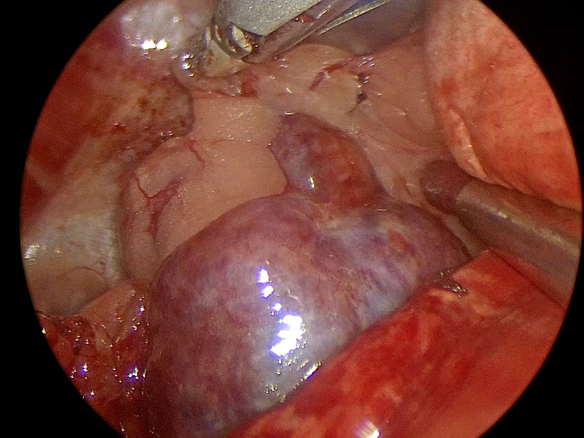

手術中の様子

胸腔鏡下での腫瘤病変の確認

摘出した後に特殊な回収袋で回収

摘出した腫瘤病変(病理検査結果:胸腺腫)